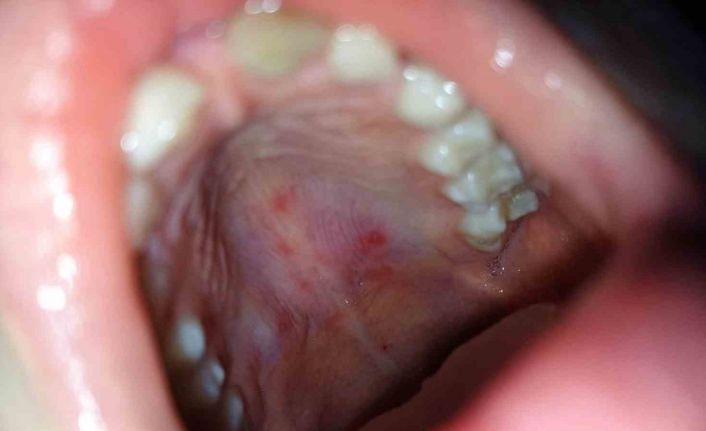

Hastalığın belirtileri ve dikkat edilmesi gereken hususlardan bahseden Medicana International Samsun Hastanesi Çocuk Sağlığı ve Hastalıkları Uzmanı Dr. Mustafa Alper Aykanat, “Ateş, boğaz ağrısı, dil, diş etleri ve yanakların iç kısmında kabarcık şeklinde lezyonlar, avuç içi ve ayak tabanlarında döküntü, bebek ve küçük çocuklarda huzursuzluk, iştah kaybı ve yutma zorluğu şeklinde belirtileri vardır. El-ayak-ağız hastalığı, küçük RNA virüsleri olan döküntülü bir hastalıktır. Hastalık damlacık yoluyla bulaşır bu nedenle okul ya da kreşteki çocuklar arasında bulaşması kolay olur. El- ayak-ağız hastalığı şüphesi olan çocuklarda pediatri hekimi çocuğun bilgilerini aileden aldıktan sonra fiziki muayeneyi yaparak tanısını koyar. Laboratuvar tetkikleriyle de desteklenir. El-ayak-ağız hastalığı tedavisi için özel bir uygulama yoktur. Bu hastalığının belirtileri genellikle 7 ila 10 gün içinde düzelir. Ağız yaralarının ağrısını hafifletmek için topikal oral anestezikler, çeşitli ağrı kesici ateş düşürücüler semptomları azaltmak için kullanılmaktadır. Hastalık döneminde sıvı tüketiminin artırılması, liften zengin, probiyotik içerikli gıdalarla beslenilmesi iyileşme açısından önemlidir. Ayrıca çocuk hastalık süresince dinlendirilmelidir” dedi.